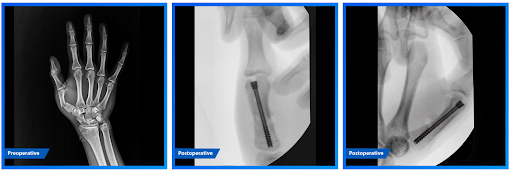

¿Dolor súbito en el codo y pérdida de fuerza al doblar el brazo o girar el antebrazo? Puede tratarse de una rotura del bíceps distal. Con técnicas quirúrgicas mini invasivas, es posible reparar el tendón con incisiones mínimas, menor dolor y una recuperación más rápida.